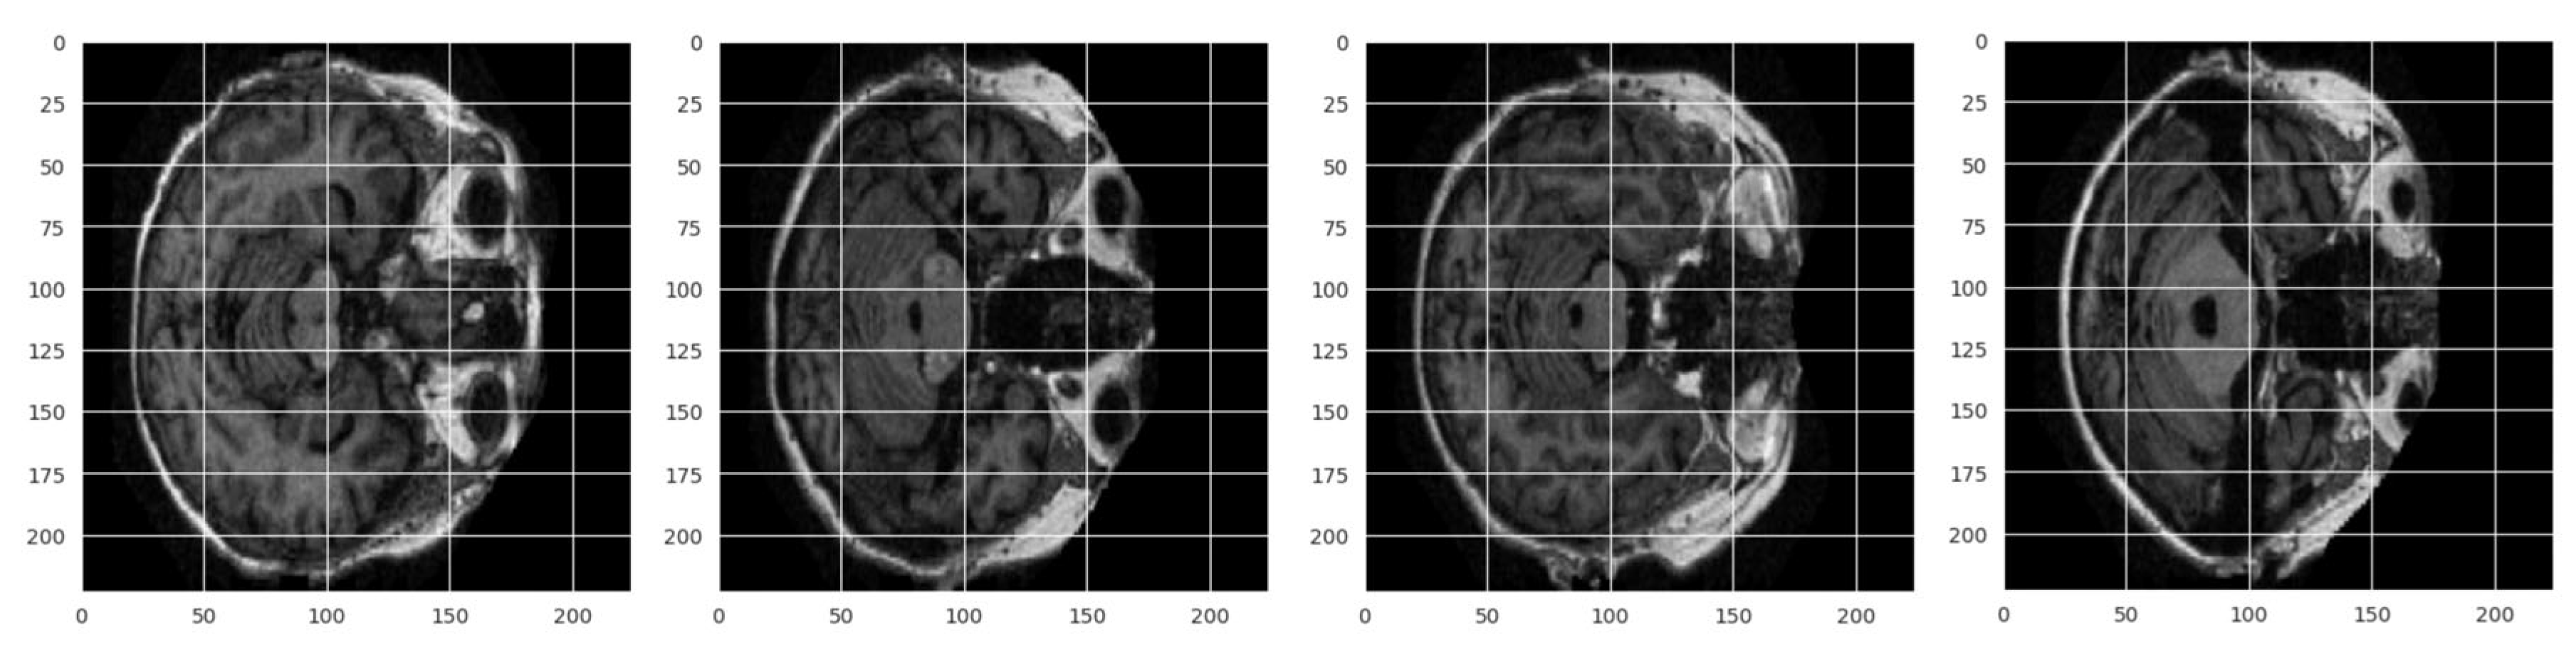

3.1. Dataset Description

3.2. Preprocessing